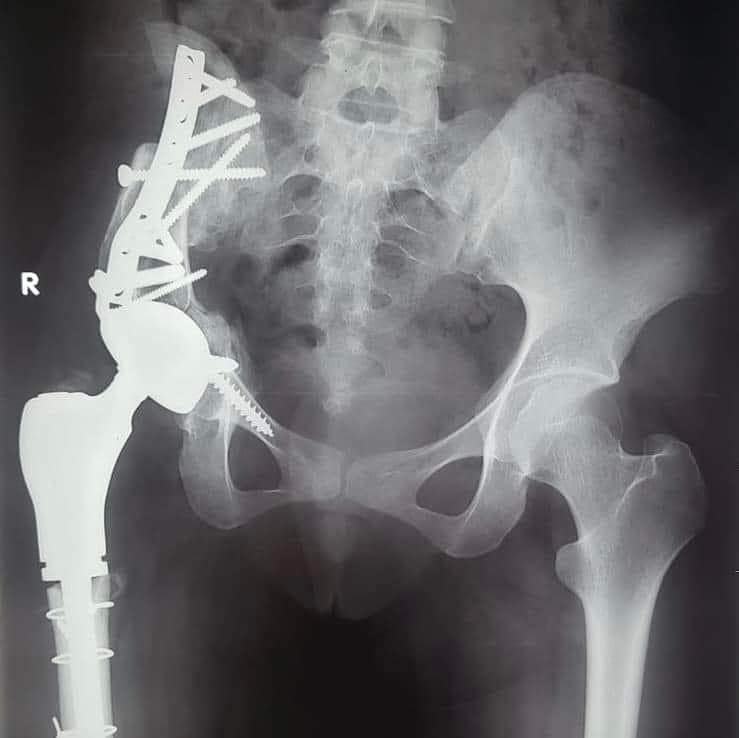

من جانبه، قال الدكتور علاء عطية عميد كلية الطب جامعة أسيوط ورئيس مجلس إدارة المستشفيات الجامعية، إن العملية الجراحية التي تم إجراؤها كانت على جانب كبير من الخطورة، مبينًا أنه تم إجراء عملية إزالة للورم، واستئصال العظم المصاب بالسرطان، ونقل الجزء العلوي من عظمة الفخذ لتحل محل عظمة الآلية.

وأوضح الدكتور عمرو السيد علي أستاذ جراحة العظام، واستشاري الجراحات الميكروسكوبية جامعة أسيوط، أن المريضة تبلغ من العمر 15 عامًا، وكانت تعاني من وجود ورم في عظمة الآلية، ومفصل الحوض؛ مشيرًا إلى إجراء العملية الجراحية على مرحلتين في إطار زمني 3 شهور؛ لتجنب البتر؛ حيث تم في المرحلة الأولى إزالة الورم من عظمة الآلية، ونقل الجزء العلوي من عظمة الفخذ؛ لتحل محل عظمة الآلية.

وأوضح الدكتور محمد مهران أستاذ جراحة العظام المساعد، واستشاري جراحات تغيير المفاصل الصناعية جامعة أسيوط، أنه تم -بعد إجراء الفحوصات الطبية- تركيب مفصل صناعي كامل ذي مواصفات خاصة للحوض، وذلك دون اللجوء لتثبيت المفصل، ولتجنب البتر لهذا الطرف؛ مشيرًا إلى نجاح العملية واستقرار الحالة الصحية للمريضة، وتمت متابعتها؛ لحين عودة حركة المريضة لصورتها الطبيعية، مشيرًا في الوقت نفسه أنه تم نشر العملية الجراحية عالميًا: في مجلة علمية متخصصة للحالات الصعبة؛ بمساعدة الدكتور أحمد عادل خليفة مدرس جراحة العظام بكلية الطب جامعة جنوب الوادي.